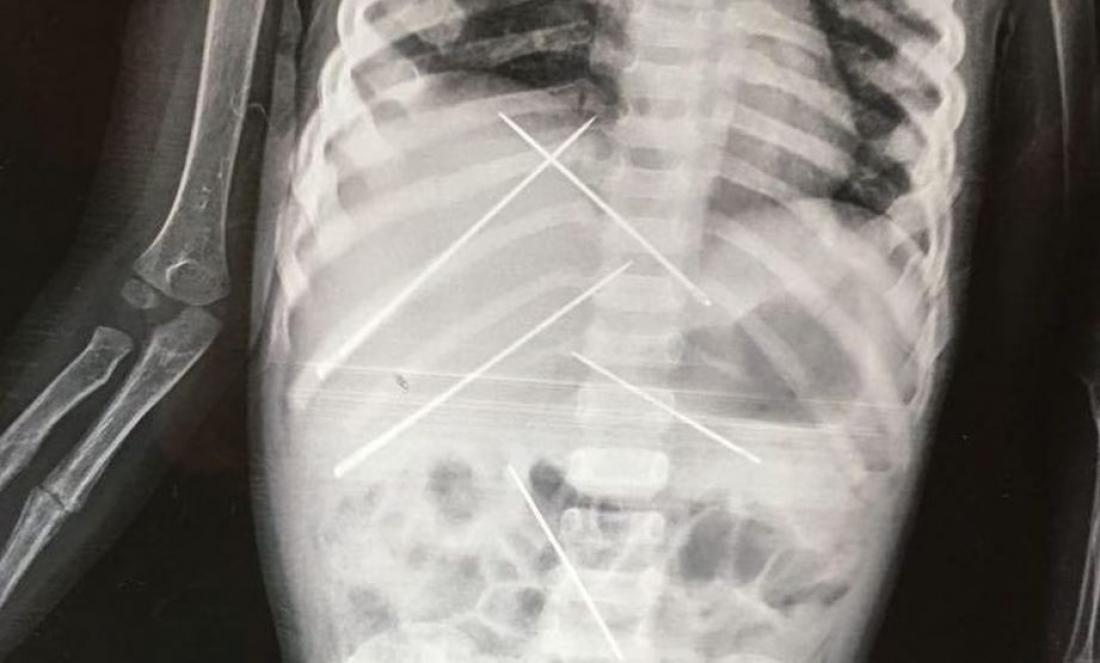

Όταν υποβλήθηκε σε ακτινογραφία, οι γιατροί αντίκρισαν ένα πρωτοφανές θέαμα. Σχεδόν 10 μεγάλες βελόνες είχαν καρφωθεί μέσα στο σώμα του 3χρονου κοριτσιού, σε διάφορα σημεία. Επίσης, το ένα χέρι του παιδιού ήταν σπασμένο.

Το 3χρονο κορίτσι υποβλήθηκε σε εγχείρηση και της αφαιρέθηκαν οι βελόνες μέσα από το σώμα της.